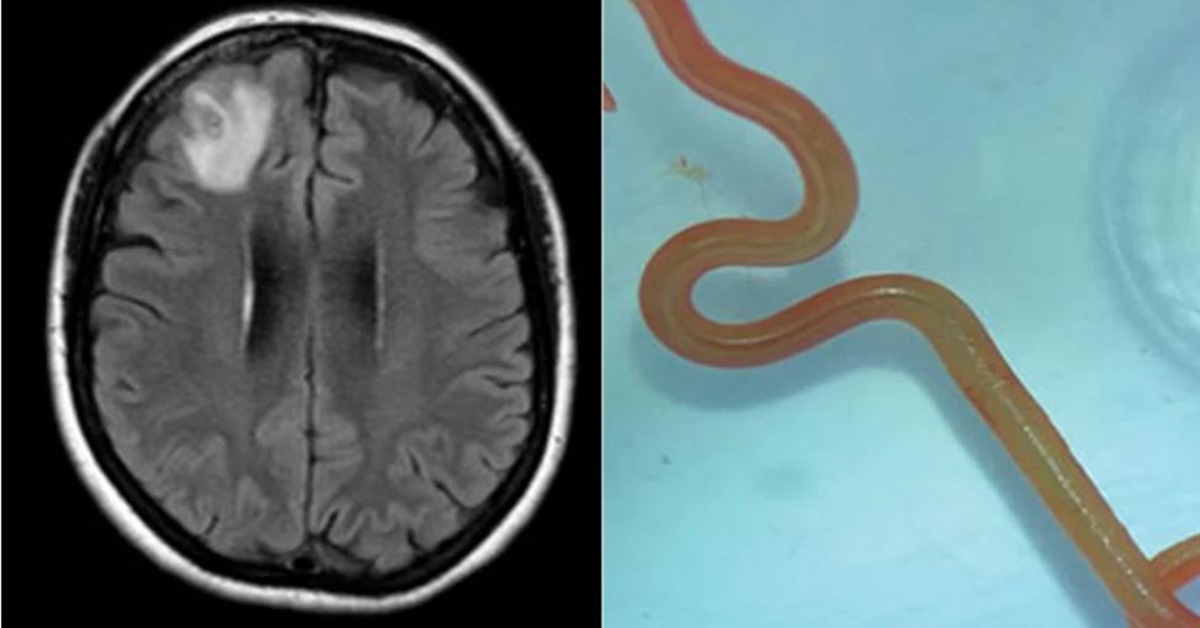

ซิดนีย์ 29 ส.ค.- คณะแพทย์ในออสเตรเลียดึงพยาธิตัวกลมที่ยังมีชีวิตและดิ้นได้ ออกจากสมองของคนไข้สตรีรายหนึ่ง เป็นพยาธิที่ปกติแล้วพบในงู

วารสารโรคติดเชื้อเกิดใหม่ (Emerging Infectious Diseases) รายงานว่า คณะแพทย์ในออสเตรเลียได้ใช้วิธีเอ็มอาร์ไอ (MRI) ตรวจคนไข้สตรีชาวออสเตรเลียวัย 64 ปี หลังจากเธอมีอาการหลงๆ ลืมๆ ผลตรวจพบรอยโรคผิดปกติที่สมองส่วนหน้า และพบพยาธิตัวกลมขนาด 8 เซนติเมตรชื่อโอฟิดาสการิส โรเบิร์ตซี (Ophidascaris robertsi) เป็นพยาธิที่มักพบในจิงโจ้และงูหลามคาร์เพต ครั้งนี้จึงเป็นครั้งแรกในโลกที่พบพยาธิชนิดนี้ในคน และเป็นครั้งแรกที่พบพยาธิชนิดนี้ในสมองของสิ่งมีชีวิตอื่น

นักวิจัยสันนิษฐานว่า คนไข้ได้รับพยาธิจากการเก็บพืชผักใกล้บ้านมารับประทาน ซึ่งอาจปนเปื้อนไข่พยาธิที่ออกมากับอุจจาระของงู.-สำนักข่าวไทย